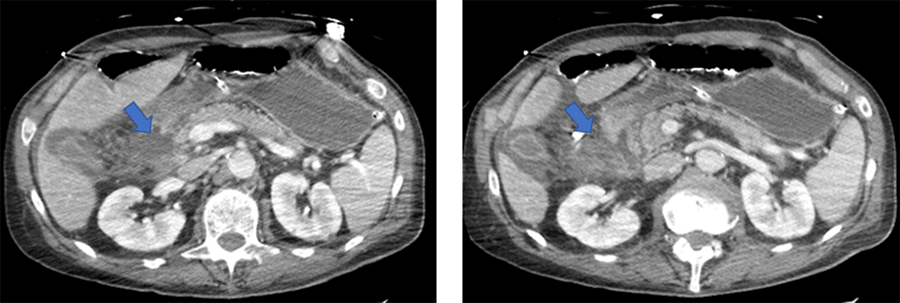

Computed tomography (CT) pan imaging and x-rays of his extremities were performed to evaluate the extent of the patient's injuries. The patient sustained a small subarachnoid hemorrhage, a C1 displaced lateral mass fracture, comminuted bilateral nasal bone fractures, a right maxillary sinus fracture, a right zygomatic arch fracture, a sternal fracture, bilateral rib fractures, pneumomediastinum, a closed left femoral neck fracture, an open displaced comminuted fracture of the left femoral shaft, a left supracondylar humeral fracture and a pancreatic contusion. The pancreatic contusion was described as stranding of the peripancreatic fat. Some of these findings were thought to be in part, related to motion artifacts (Figure 1).

Figure 1. Initial CT Imaging of Abdomen and Pelvis After Traumatic Injury. Published with Permission

Imaging was suggestive of pancreatic contusion, described as stranding of peripancreatic fat (arrow); some of these findings were thought to be in part related to motion artifact.